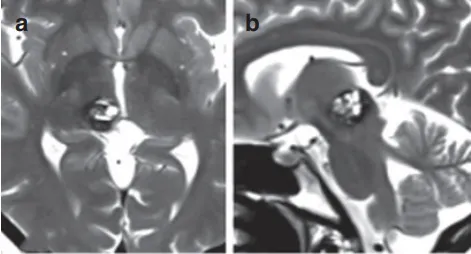

37岁的Anne,被松果体区的一颗海绵状血管瘤纠缠了整整7年,这颗“不定时炸弹”像是一个沉默的侵略者,悄无声息地逐渐膨胀,让Anne的日子越来越不好过。这几年,她的左侧身体开始不对劲,脸麻、站不稳,连说话都有点儿含糊了。去医院一查,磁共振MR就如同透视眼一般,清晰地揭示了这颗直径达15毫米的“恶魔”藏身之处——中脑上部与右侧丘脑之间,一个极为复杂且危险的区域。

术前MRI影像

松果体区,要想找到这大脑的正中心位置,同时不损伤到周围的脑组织,这就要求找到脑组织之间的缝隙,以庖丁解牛的精神,精雕细琢来完成手术。手术需要手术者极大的耐心与精细操作,对手术者来说是极大考验。